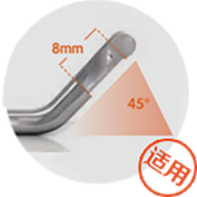

Break away from traditional treatment根据患者腋下的弧度选择适合患者最佳角度的手柄刀头量身定制祛臭专属方案。

大汗腺数量、范 围、深度广泛的 重度腋臭、多汗 多毛的复合型腋臭等